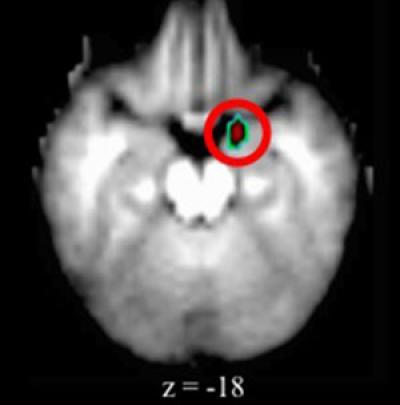

Depressed preschoolers had elevated activity in the brain's amygdala, an almond-shaped set of neurons important in processing emotions. Earlier imaging studies identified similar changes in the amygdala region in adults, adolescents and older children with depression, but none had looked at preschoolers with depression.

Brain scans of preschoolers with depression revealed elevated activity in the amygdala (the small area in the red circle) when compared with scans of young children exhibiting no signs of depression.

(Photo Credit: Washington University School of Medicine.)